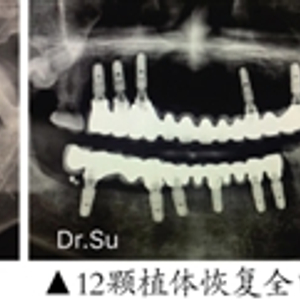

72岁的吴叔是一位退休大学教授,此前全口牙基本掉光,种牙前以为要缺一颗种一颗,一直拖着没敢种,苏凯主任给吴叔介绍了“ALL-ON-N”种植技术,拔除牙齿残根后,种了12颗植体就恢复了整口牙,费用也省了一大半。近日,吴叔回到医院进行复诊,术后恢复情况良好,咬合关系正常。吴叔开心表示,现在想吃什么就吃什么,身体也好了不少。